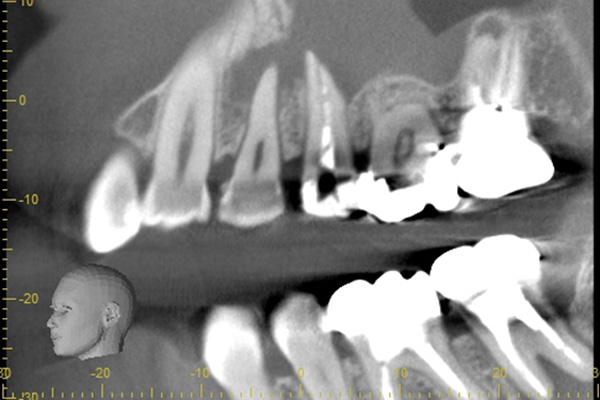

こちらは根の中の防腐剤が疎で、最近が繁殖するスペースをあたえてしまっていたため、患者様に違和感を感じさせていました。そこで、中の防腐剤を取り除き、それをCTとマイクロスコープで確認し、清掃を行い、今度は緊密に防腐剤を入れていきました。

こちらは根の治療の経験がある歯ではありませんが、歯茎が大きく腫れていらした患者様です。レントゲンを撮ってみると原因となっていそうな、2本怪しい歯がありました。過去の虫歯の経緯から後ろの歯の方が怪しいと判断し、1本だけ治療を行いました。

治療後、腫れの大きさの確認のためにCTを撮影すると、上顎洞にまでおよぶ大きな炎症があり、骨が大きくなくなっていることが確認できました。

基礎に忠実に根の中をしっかり清掃し、防腐剤を詰めて経過をみるために3ヶ月後に再度CTを撮影しました。以前とは比べ物にならないくらい、上顎洞の炎症はなくなり。上顎洞を隔てる骨の再生もできました。 またこの治療で一番良かったのは、治療しなければならない歯とそうでない歯を鑑別できたことです。手前の歯はやはり治療する必要がなかったのです。

初診終了後にCT撮影です。上顎洞と歯が連続してしまうくらい炎症が広がっています。